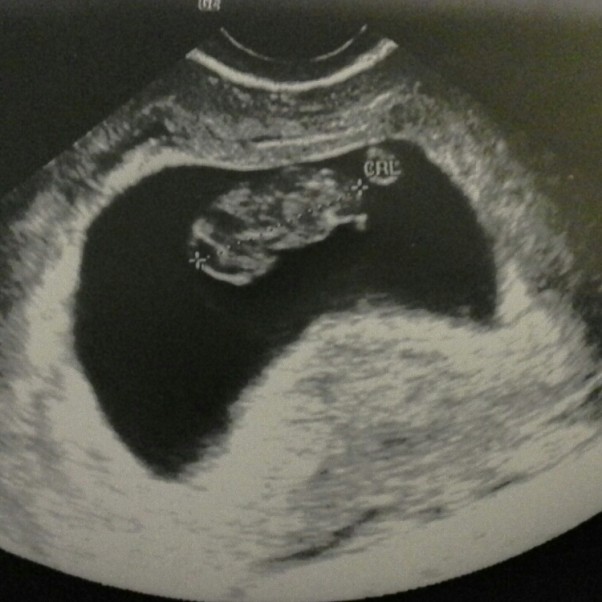

8 tydzień

Wizyta u ginekologa i diagnoza, to 8 tydzień,za dwa tygodnie druga wizyta, proszę zrobić dokładne usg i przyjść. Wczoraj było usg i diagnoza 8 tydzień i 5 dzień. Serduszko bije mocno. Termin porodu 18.12. Rośnij nasz Bąbelku!